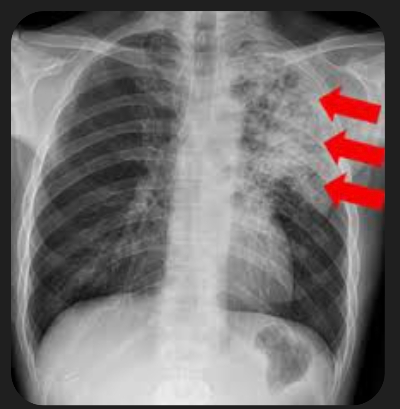

5. 폐렴 증상

폐렴 증상은 질환이 진행되면서 다양하고 심각하게 나타납니다. 주요 증상으로는 고열, 후두통, 가래를 동반한 강한 기침, 흉통, 호흡곤란, 빠른 호흡 등이 있습니다. 가래는 화농성으로 노란색이나 녹색을 띕니다.